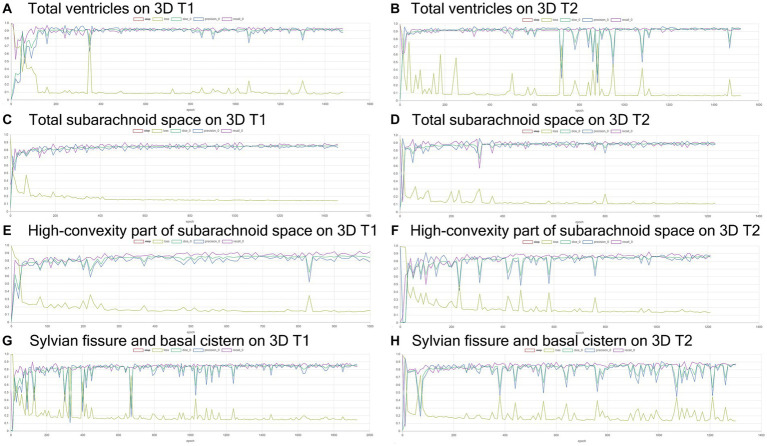

Volumetric semantic segmentation

Training and internal validation of the 3D U-Net model for semantic segmentation were repeated over 1,000 times (Figures 4–7; Supplementary Figures S1, S2). Overall, the intracranial CSF space, total ventricles, total SAS, Sylvian fissure and basal cistern, and the high-convexity SAS were segmented fully automatically from 3D T1-weighted (Figure 8) and T2-weighted MRIs (Figure 9). There was no significant difference between manually and automatically segmented volumes of the total ventricles, total SAS, high-convexity SAS, and Sylvian fissure and basal cistern (Table 3). Among the segmented regions, the mean Dice scores for the total ventricles were highest (0.85 from T1 and 0.83 from T2), those for the Sylvian fissure and basal cistern were second highest (0.70 and 0.69), and those for the high-convexity SAS were lowest (0.68 and 0.60). The mean Dice coefficient scores for all of the regions segmented from the T1-weighted image were superior to those from the T2-weighted image. The mean differences between the manually and automatically segmented volumes of the high-convexity SAS were smaller (T1 and T2; 3.6 mL and 4.2 mL) than those of the Sylvian fissure and basal cistern (5.3 mL and 8.3 mL).